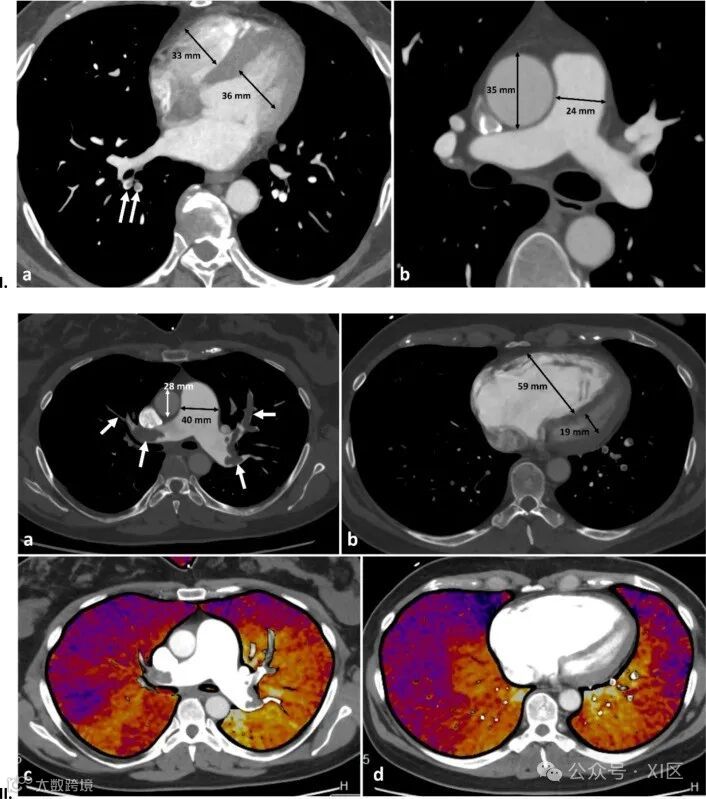

双能量CT(DECT)通过两种不同的X射线光子能谱来描绘组织的衰减特性,从而获取比单能量CT更丰富的物质组成信息。DECT生成的虚拟单色图像可用于提高对比噪声比并减少PE评估中的对比剂需求。DECT碘分布图可用于评价灌注缺损,研究显示其能够检测到CTPA上未见的额外段或亚段PE。 (更多内容参见XI区:双能量CT在肺栓塞中的应用) 。

此外,减影CT也是一种评估CTPA灌注的手段,通过从对比增强图像中减去预先采集的无增强图像来生成运动校正的碘分布图。加上碘图后,CTPA可更好地直观显示肺灌注,在一项研究中显示与DECT碘图相比,减影CT碘图在特异性上有小幅提升。然而,减影CT碘图的临床应用价值可能有限,且大规模前瞻性研究仍需进一步探索其在诊疗中的作用。

双源CT肺栓塞双能量评估